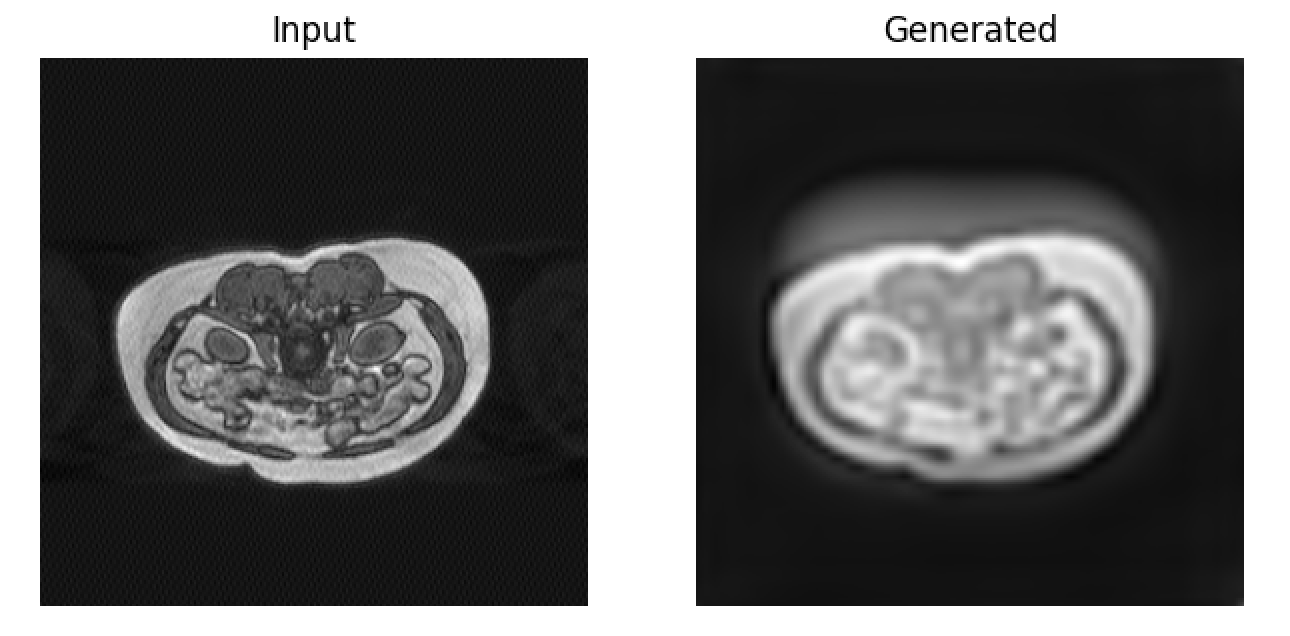

Visual inspection of results revealed substantial attenuation of ghost streaks and k-space spike artifacts without introduction of hallucinated anatomical structures. The perceptual loss component particularly enhanced preservation of fine hepatic vasculature, with right hepatic vein structures (approximately 2-pixel diameter) maintaining appropriate contrast and definition, as shown in Figure 3.

Artifact-specific performance:

• Ghosting artifacts: 85% reduction in streak visibility

• Motion blur: Restoration of edge definition in liver boundaries

• Spike artifacts: Complete elimination of bright spot distortions